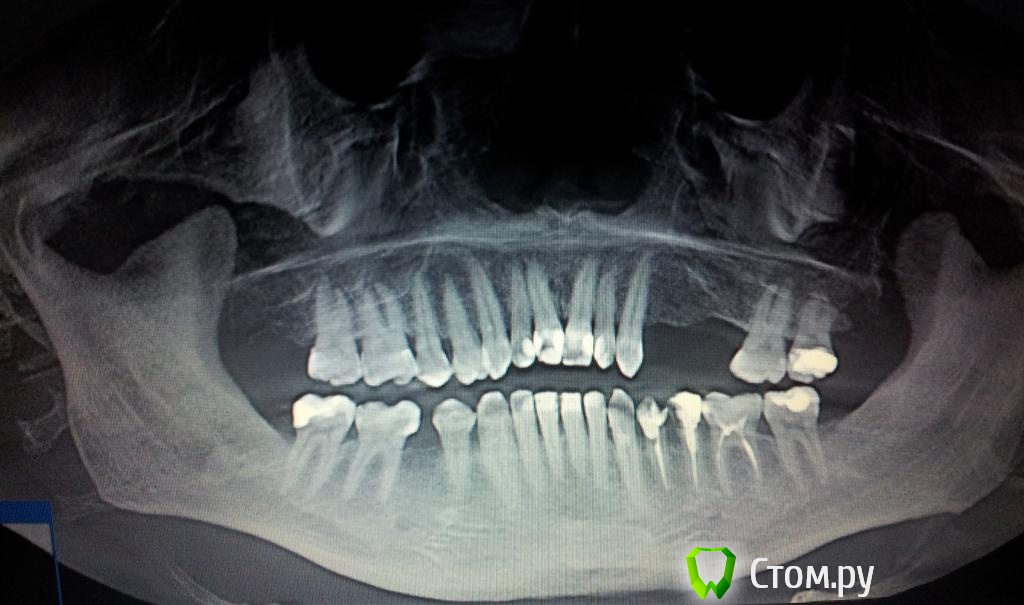

Пациент Ю Опубликовано 24 марта, 2014 Автор Поделиться Опубликовано 24 марта, 2014 Вот и удалили имплант. теперь три месяца ждём. А пока снимки что есть на руках. Виноватых не найти. Все по своему правы. Ссылка на комментарий

Пациент Ю Опубликовано 25 августа, 2014 Автор Поделиться Опубликовано 25 августа, 2014 ...продолжаем, только теперь со смещением и синус-лифтингом. Кости мало, и только с синус-лифтингом можно поставить имплант, и только не в то же место. Опять деньги в кассу! За материалы - костный и мембрану. Врач любезно согласился работу по установке провести без участия моих средств..Ну хоть так. Никаких гарантий, может ещё и имплант не поставит сразу... 6 месяцев ждать в таком случае а. потом ещё 6 месяцев. После чего история может и повториться. А куда потом ставить?! Смещать же будет некуда)) печалька. Вообщем что хочу сказать: если у Вас есть деньги - храните их в сберегательной кассе, или потратьте их в дорогой клинике, на дорогие импланты и работу высококвалифицированного персонала, который сделает всё (за Ваши деньги конечно), и упаси Вас бог повестись на дешёвый имплант mis и клинику где их ставят. В таких вот случаях репутация mis - Ваше мнение? (ответьте себе сами). Ведь для её поддержания, mis могла бы материалами то и помочь, раз уж клиника не стала. Ссылка на комментарий

SDC Опубликовано 7 сентября, 2014 Поделиться Опубликовано 7 сентября, 2014 Вот и удалили имплант. теперь три месяца ждём. А пока снимки что есть на руках. Виноватых не найти. Все по своему правы.Ю, Вы хороший человек. Хочется пожелать Вам удачи и хорошего лечения.Пока есть время, займитесь антагонистами - велик риск их перелома, когда появятся коронки на имплантатах на в.ч. Ссылка на комментарий

Пациент Ю Опубликовано 28 декабря, 2014 Автор Поделиться Опубликовано 28 декабря, 2014 Давно тут не был... Вообщем не поставил врач имплант пока. А разрезав десну, нарастил костным материалом кость в ширину.., как бы в феврале надо делать синуси устанавливать опять имплант. Вот такая долгая история. Как тут заметили и посоветовали не экономить, но какая тут экономия?! Тут или так или вообще никак! Не миллионер я к сожалению, а зубы то нужны. По поводу антогонистов и их лечения, то да - это надо, но опять же - протезов у меня пока не установлено, и если всё удачно будет, то не раньше чем через год. В таком случае лучше не трогать пока ещё нормальные зубы. Знал бы что так всё будет - долго и дорого, то и не думал бы ставить импланты, а теперь вот вписался и вроде бросать на полдороги не хочется. Ссылка на комментарий